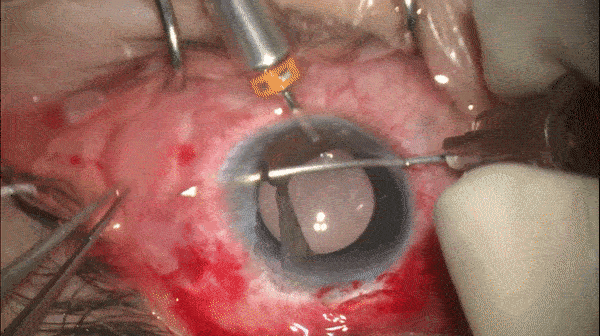

Step 10

无瓣膜巩膜缝线固定对侧攀

对侧攀重复步骤8和步骤9的操作。(图示完成后)

Step 11

埋线

将锚结和游离端缝线置于30G针头,随后从先前巩膜穿刺口进针,平行于角膜缘在巩膜中穿行约3.0-4.0mm后穿出,以完成巩膜层间穿行。对侧重复操作。

观察IOL的居中性,进一步微调缝线张力,剪去眼外多余缝线,将尾端埋入巩膜内。